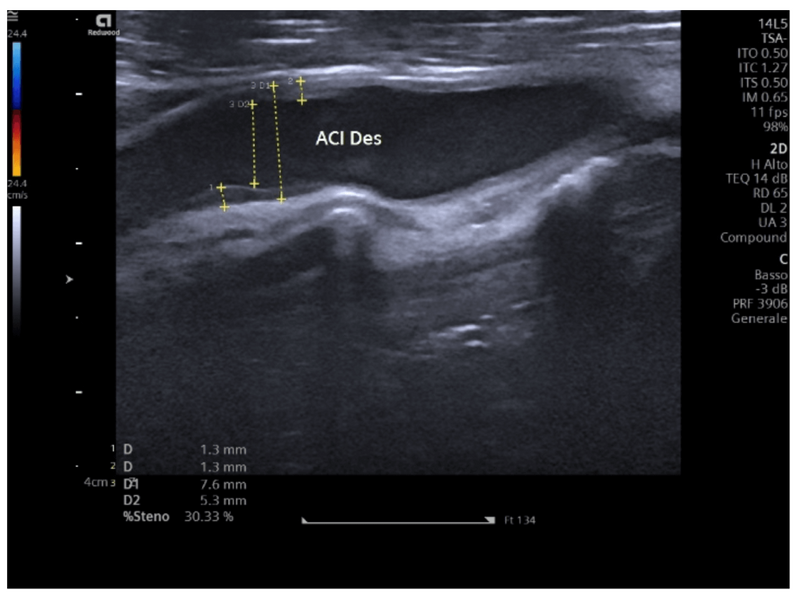

Ecodoppler van de supraaortale stammen

Niet-invasief onderzoek van halsslagaders en vertebrale arteriën voor evaluatie van de circulatie naar de hersenen...